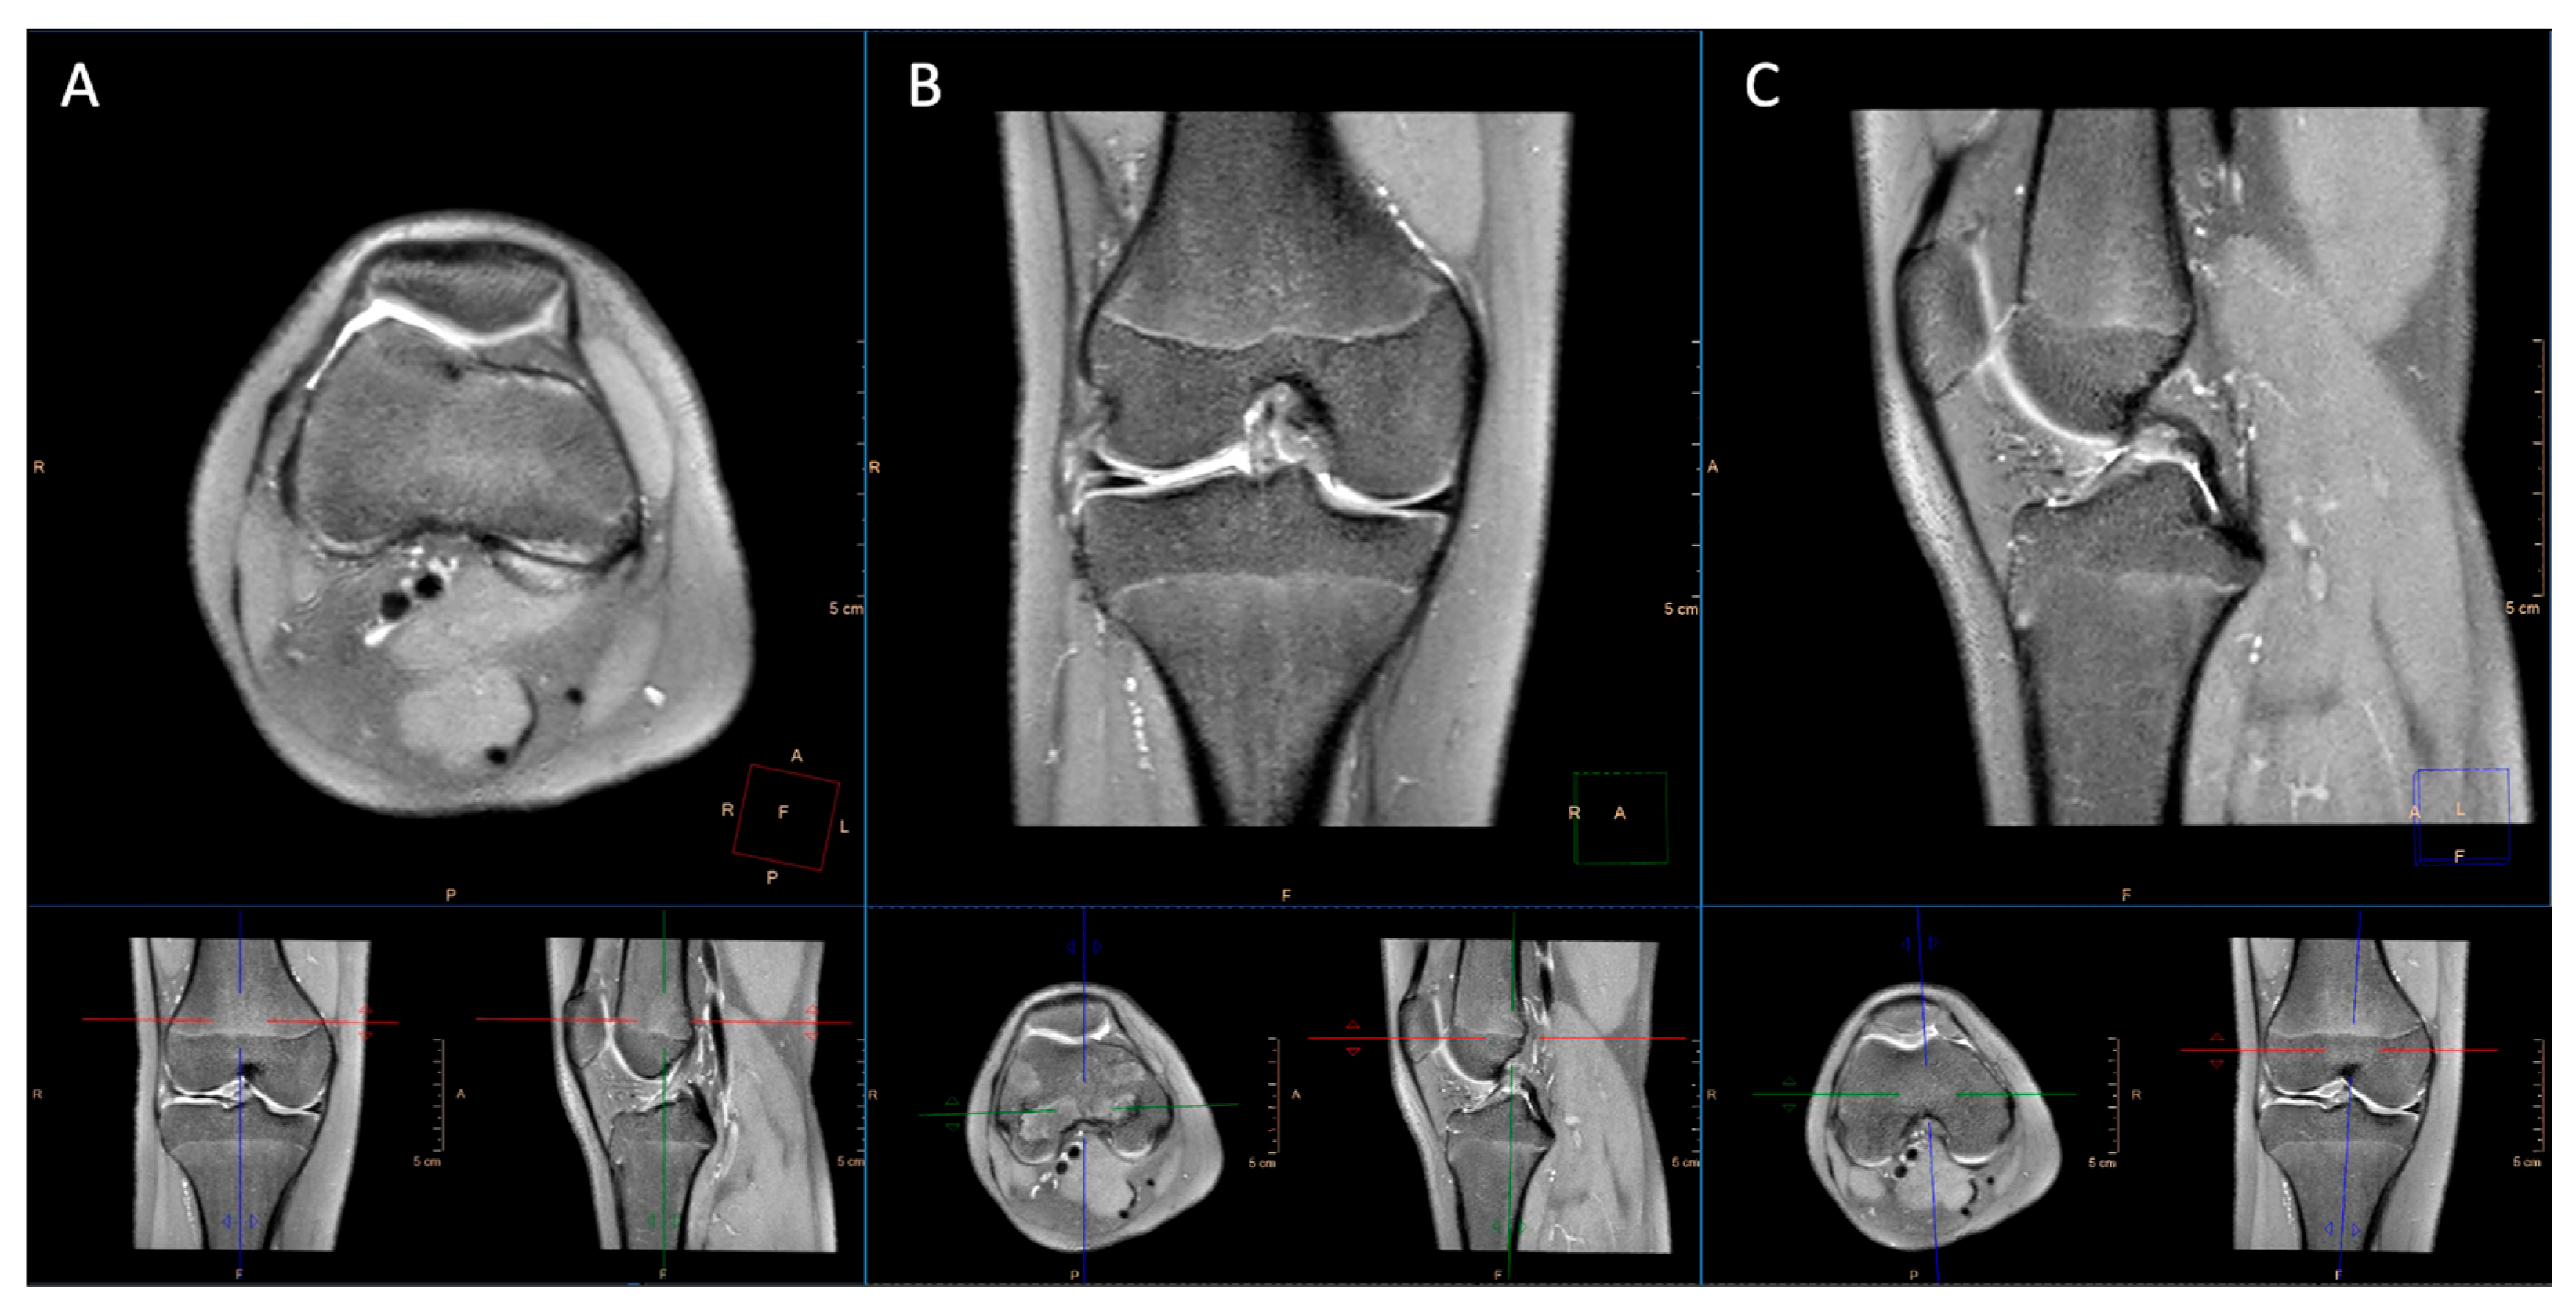

2.2. Imaging Technique

3.1. Image Quality

4. Discussion